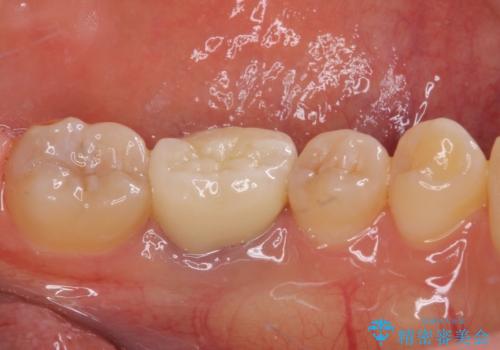

仮歯に置き換えた時点で希望に近い形態とできたので、その形を踏襲してオールセラミッククラウンを製作してもらいました。

気になっていた形が改善され、色調も自然なものとなったので、患者様には大変満足していただきました。